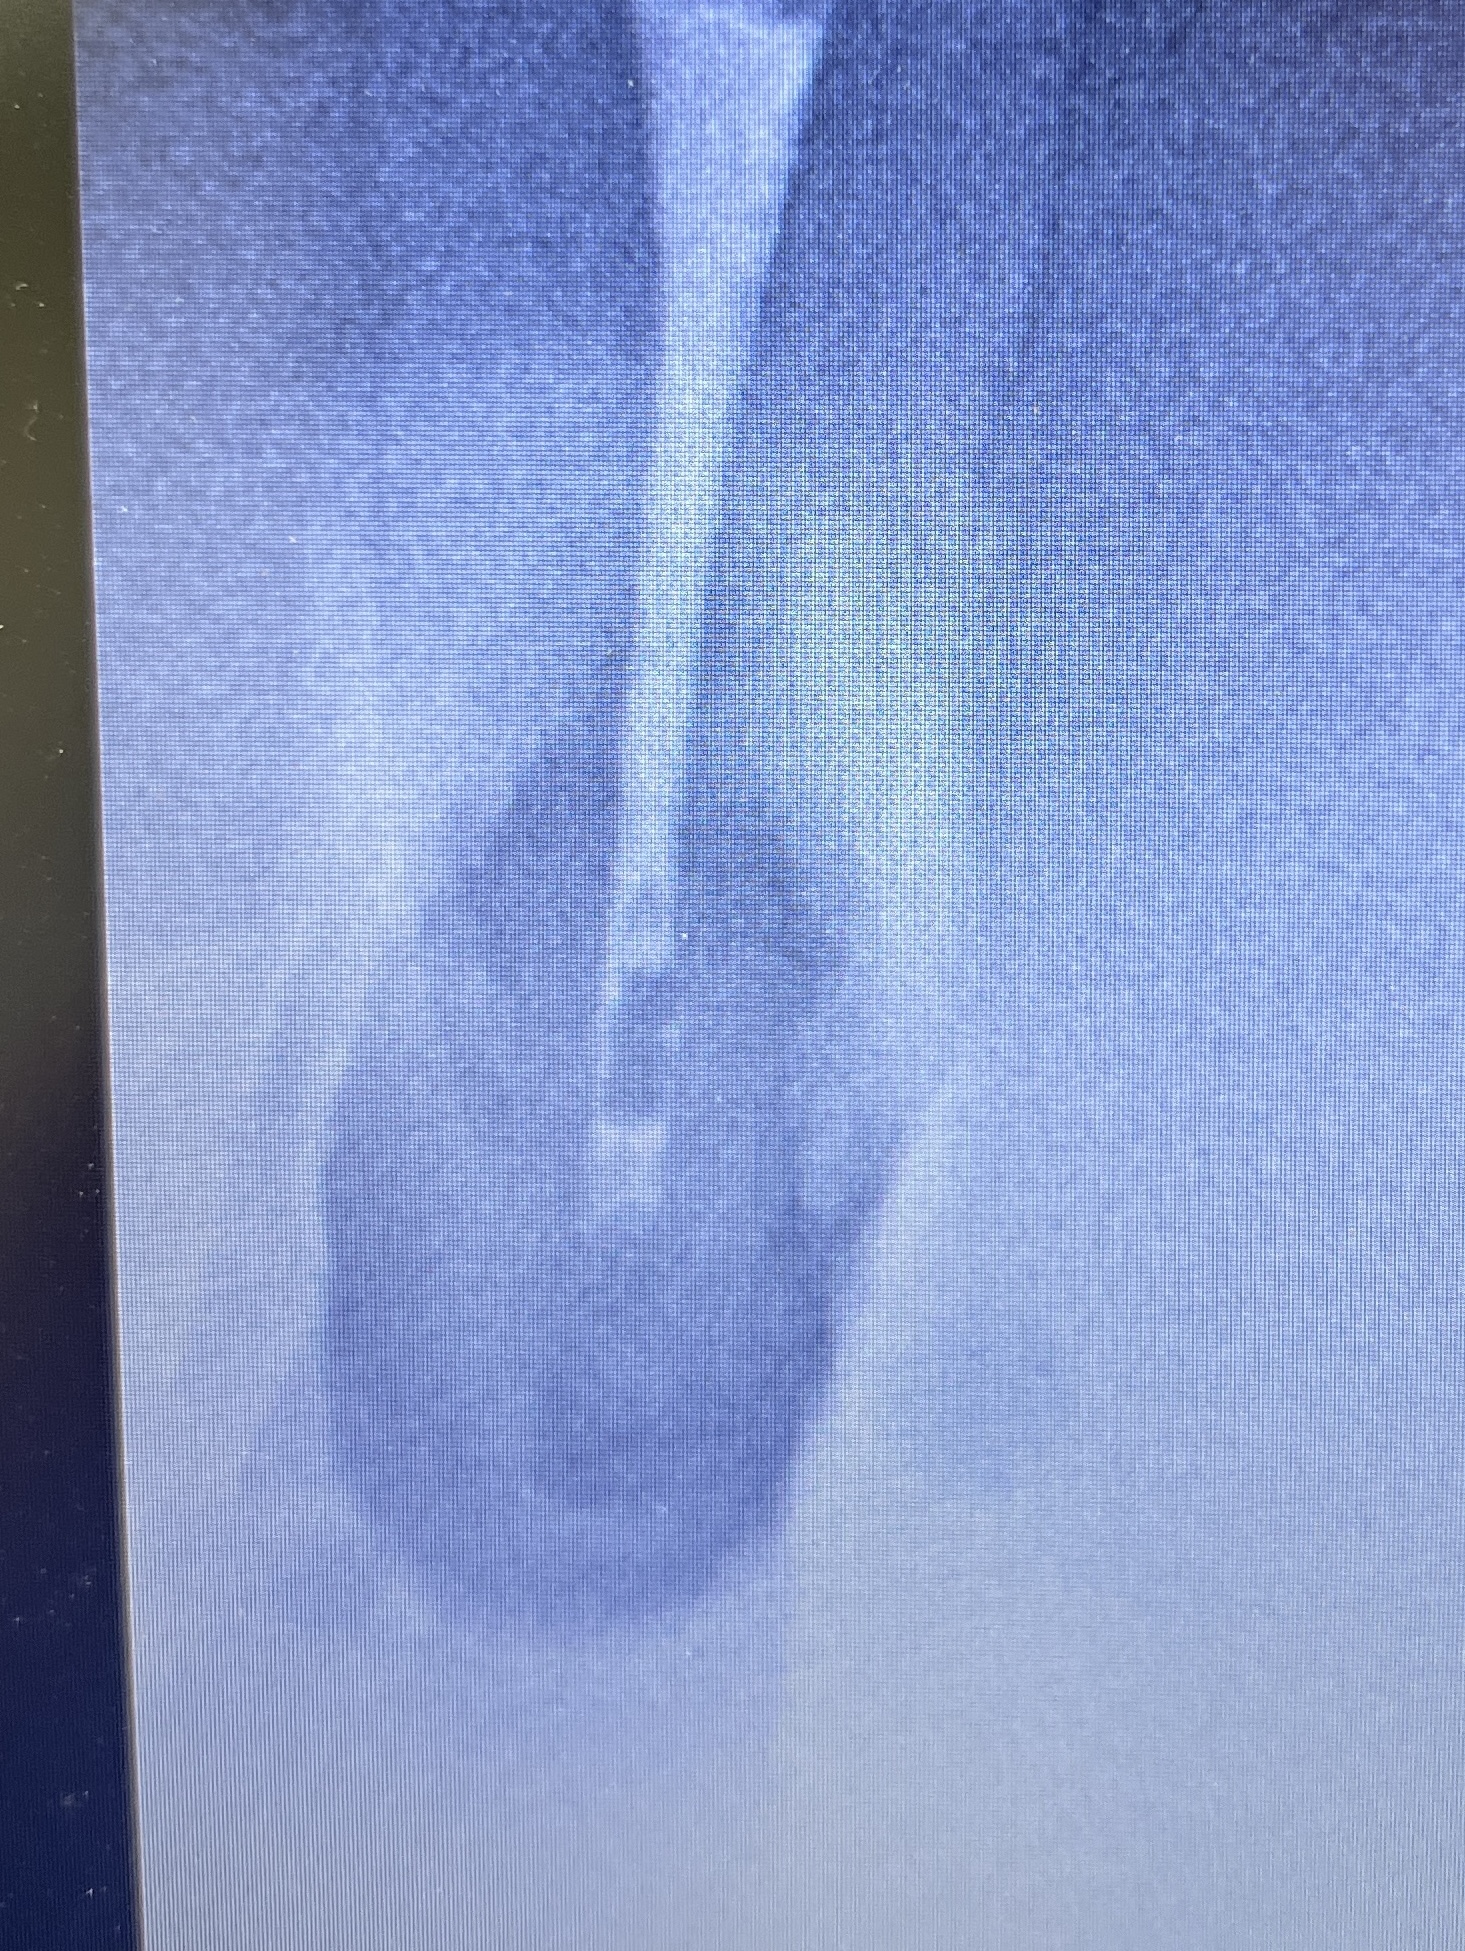

ここで、撮影をしてもらったCBCTを公開しよう。以下である。

これは私なら、もっと切断してやり直すだろう。

絵が、しょっぱいからだ。